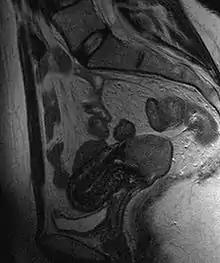

Often before the biopsy, the doctor asks for medical imaging to rule out other causes of woman's symptoms. Imaging modalities such as ultrasound, CT scan, and MRI have been used to look for alternating disease, spread of the tumor, and effect on adjacent structures. Typically, they appear as heterogeneous mass on the cervix.[50]